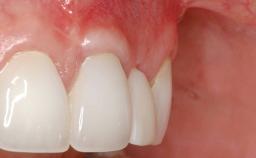

GBR and Soft-Tissue Augmentation Following Explantation to Rehabilitate a Soft- and Hard-Tissue Defect

It is sometimes necessary to remove and replace compromised implants. This case is a clear example of the need for multiple steps to achieve an optimal therapeutic result for patients with non-salvageable implants. It illustrates how the lost soft and hard tissues were rebuilt in a sequence that improved the healing of the hard tissues and assured their long-term stability. The 35-year-old healthy patient presented with clinical attachment loss on the proximal and lingual surfaces of the natural dentition. Some gingival recession was present on natural teeth, particularly in the posterior sextants (S1, S3, S4, and S6).